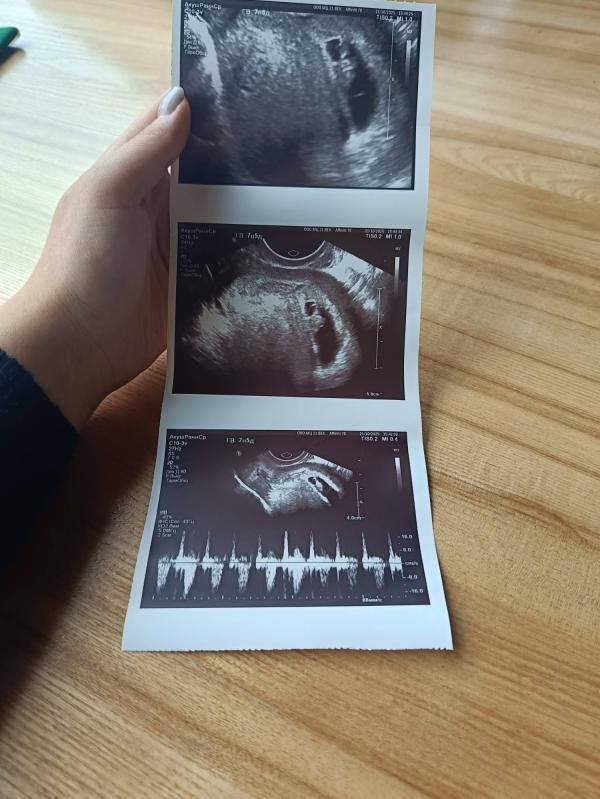

Первое сердцебиение малыша: реакция будущего папы

Наш сладкий зайчик❤

Будущий папа услышал сегодня сердечко❤ Он офигел, 🤣когда на экране показывают микро человека, а там уже во всю работает сердечко.